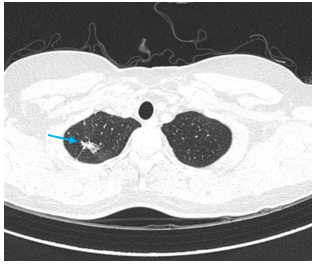

– Chụp cắt lớp vi tính lồng ngực: Nhu mô thùy trên phổi (Phải) có nốt tổn thương kích thước 13x14mm, bờ không đều, ngấm thuốc, sau tiêm. Rải rác nốt đặc 2 bên thùy phổi kích thước 3-10mm. Trung thất các nhóm 1R; 2R; 4R; 5; 8; 10RL có vài hạch lớn nhất kích thước 26x15mm; bờ không đều; ngấm thuốc không đồng nhất sau tiêm. Thượng đòn 2 bên có vài hạch tính chất tương tự; hạch bên phải kích thước 11x14mm

Hình 2: Hình ảnh cắt lớp vi tính ngực có tiêm: Rải rác nốt đặc 2 bên thùy phổi kích thước 3-10mm (các mũi tên màu xanh lá)

Hình 6: Hình ảnh cắt lớp vi tính ngực có tiêm: đám xẹp đông đặc đỉnh phổi phải kích thước 11mm (mũi tên xanh nước biển)